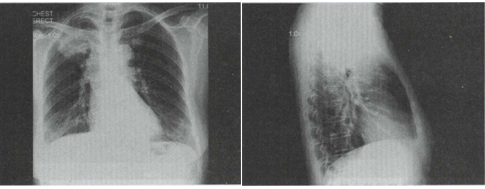

27.患者女,63岁,痰中带血2天,不咳嗽、发热,X线检查如图,最可能的诊断是 ()